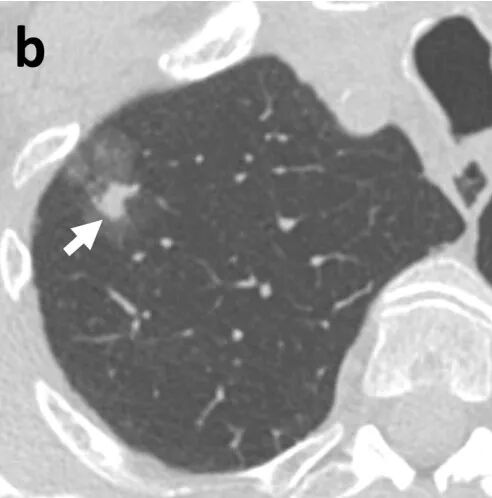

01纯磨玻璃结节

02混合磨玻璃结节/部分实性结节

03实性结节

04 囊腔型结节